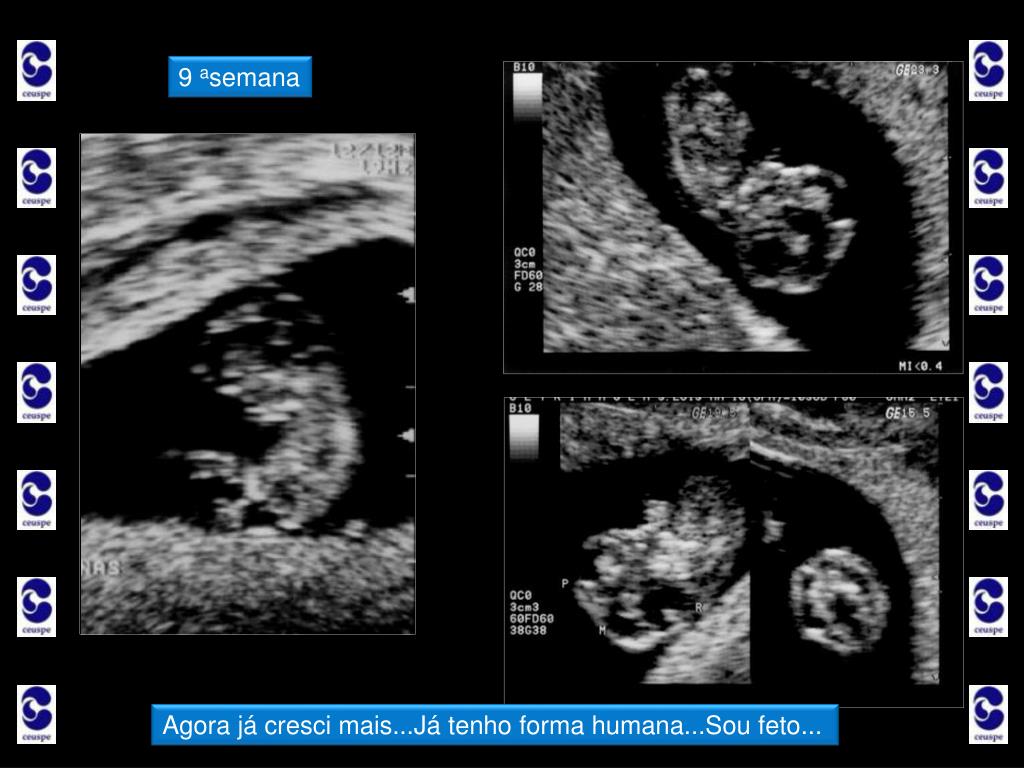

6. Ultrassonografia nos primeiros três meses... • Primeiro Trimestre • Idade Gestacional • a partir daí, o embriãozinho começa a crescer rapidamente; • já podemos medir o comprimento da cabeça até a nádega (CCN) e precisar com erro de 3 dias a idade da gravidez e data provável do parto; • na nona semana, nosso embrião passa a ser chamado de feto e já apresenta uma forma humana; • de 9 a 13 semanas, seus órgãos se formam rapidamente e seu crescimento é acelerado!

12. 9 asemana Agora já cresci mais...Já tenho forma humana...Sou feto...